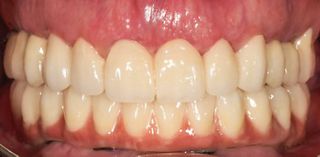

The three scan sets were imported into CAD software, aligned, and used with an implant library to connect the prostheses to titanium bases. A CAD/CAM verification jig confirmed accurate implant position capture. At the second appointment, verification jigs and prototype prostheses were tried in to assess fit, esthetics, phonetics, occlusion, and hygiene access, with minor adjustments as needed. Once approved, the STL files were sent to the lab to fabricate the definitive prosthesis, which consisted of a CAD/CAM-milled monolithic zirconia restoration with a vestibular cut-back to enhance esthetics. The prosthesis was delivered and torqued at the third appointment. The patient reported excellent satisfaction with the treatment, and clinical, intraoral, extraoral, and radiographic examinations revealed no apparent issues (Figs. 17-19).

The patient was followed for 13 months, showing stable functional and esthetic outcomes throughout the follow-up period, with good oral hygiene maintained (Fig. 20).

The patient exhibited stable functional outcomes throughout the 13-month follow-up period, with no signs of implant mobility, peri-implant inflammation, or prosthetic complications. The esthetic result was highly satisfactory, with harmonious integration of the prosthesis into the patient’s smile, natural emergence profiles, and excellent soft tissue support. Both the patient and clinician reported high levels of satisfaction regarding esthetics, phonetics, and masticatory function. The vestibular cutback in the definitive monolithic zirconia restoration enabled enhanced esthetic customization, fully meeting the patient’s expectations.

Overall, the treatment demonstrated predictable outcomes in terms of implant stability, prosthetic function, and esthetic integration, providing both clinical success and high patient satisfaction. The following images show the before and after results of the treatment (Fig. 21).